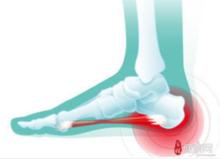

足跟骨刺是骨科的常見病、多發病,嚴重者影響生活和工作。體會跟骨刺產生的原因是跖長韌帶和跖腱膜攣縮,引起跟骨附著點處持續性的牽拉損傷。小針刀的治病機理是剝離粘連,疏暢氣血,松解肌肉,鎮痙止痛,在足跟骨刺部位套用小針刀對緊張攣縮的肌肉或韌帶進行松解,解除對足跟部附著點的牽拉損傷,從而達到“松則不痛”之目的,再以曲安縮松局部封閉,可減少滲出,防止粘連,消炎止痛,兩者合用以增強療效。

足跟痛的保養方法有:休息、選擇厚底、鞋底不能軟鞋墊軟一些的鞋子。最好後跟部有一定弧度以適應足跟的弧形;足跟部套用軟墊,如矽膠製成的跟痛墊,保護足跟減輕摩擦;功能鍛鍊。